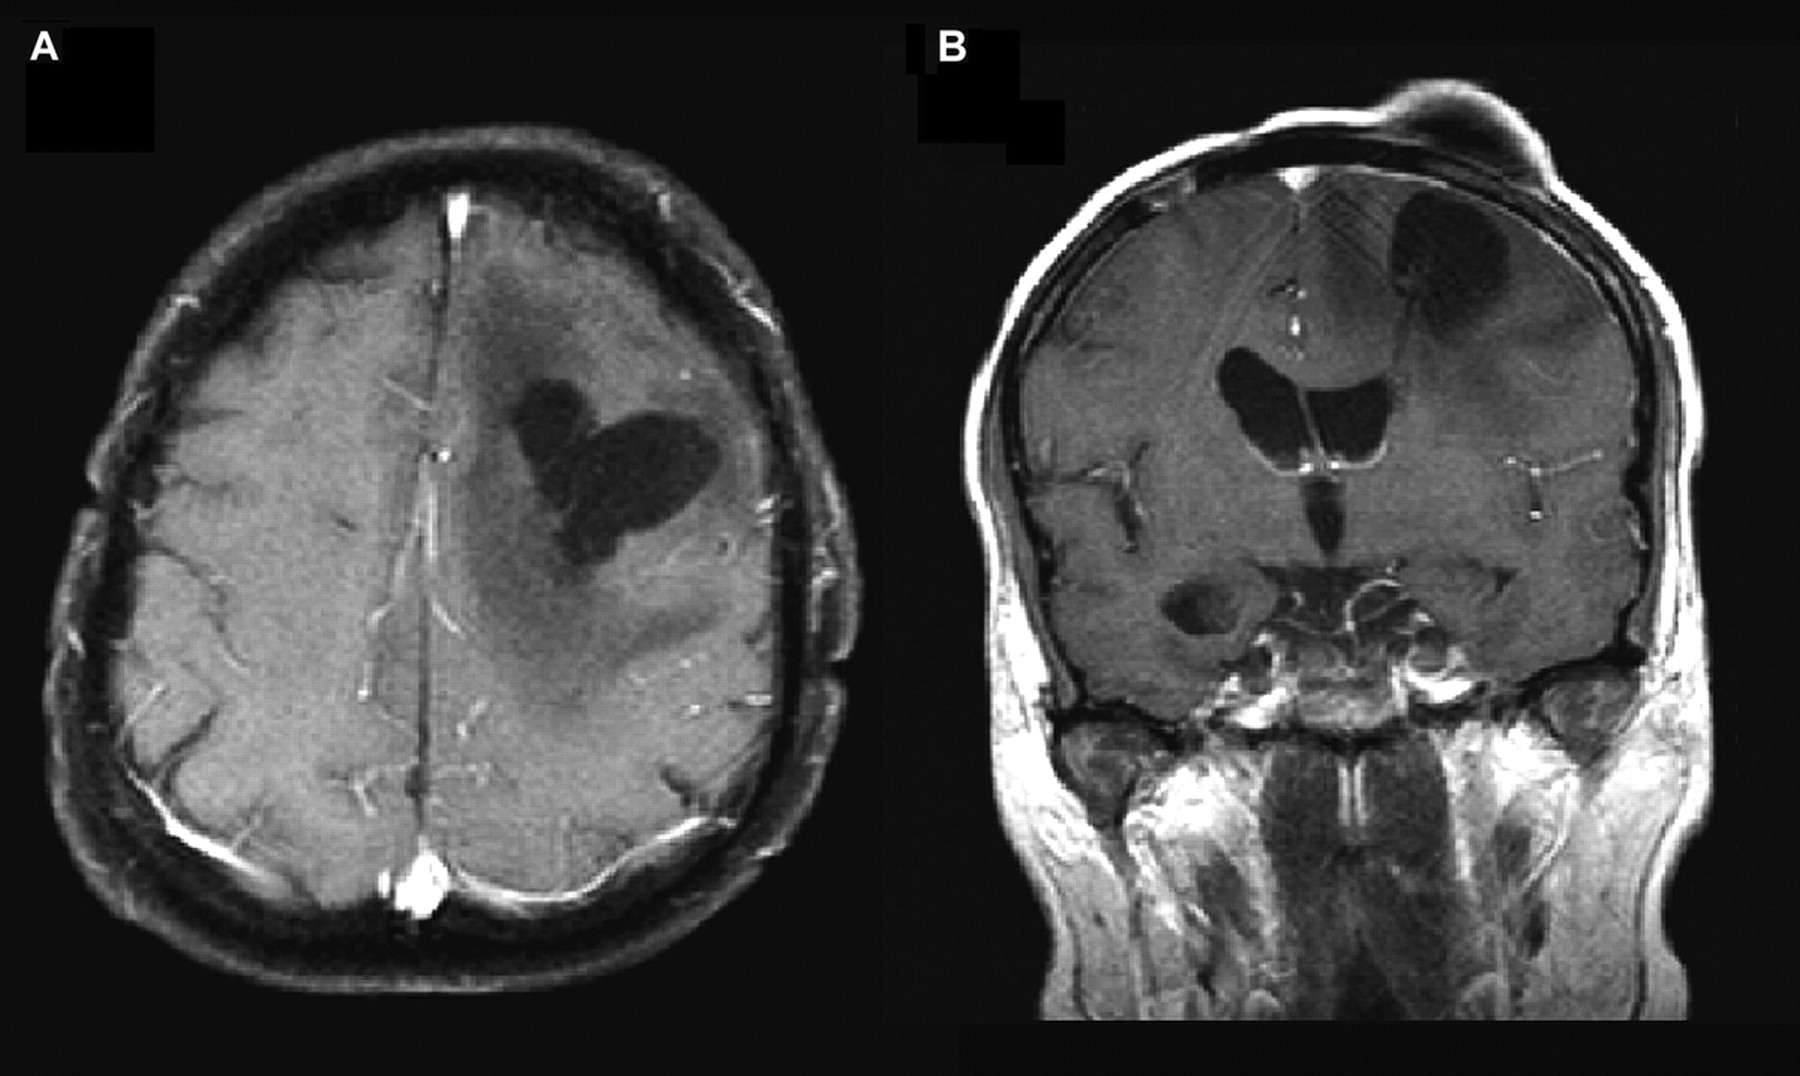

图。(A) t1轴先生形象对比演示了一个nonenhancing左额囊性空腔周围的脑室导管周围水肿。(B) t1日冕图像与对比度先生再次描述了质量效应的囊性空腔。植入奥马耶水库注意位置和脑室导管穿过囊性空腔的腔。